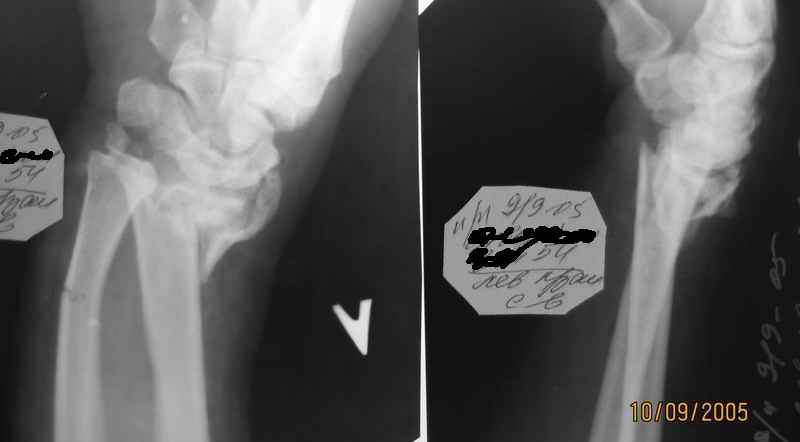

Уважаемые коллеги. Мужчина 54 года, поступил накануне-открытый перелом луча

Падение с высоты собственного роста. Перелом открытый, рана поверхностная на ладонной поверхности в проекции метэпифиза лучевой кости 1,5 см. Дежурной бригадой ПХО раны, попытка ручной репозиции, на контрольных снимках смещение остается (снимки очень низкого качества, поэтому не представляю). Какой вариант оперативного лечения лучше избрать? С уважением А. Минервин.

Абсалютное показание к внеочаговому дистракционному остеосинтезу аппаратом Илизарова за пястные кости. Судя по рентгенограмм :

Полифрактура. Откр. внутрисуставной оскольчатый перелом дистального конца лучевой кости и перелом шиловидного отростка и диафизарный перелом локтевой кости со смещением костных отломков. Для достижение идеального устранение смещений костных отломков (что очень важно для дальнейшего воостановление функции лучезапстного сустава) предлагаю по новой методики нашей клиники.